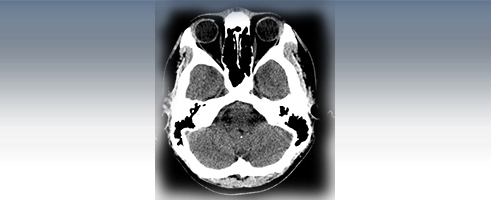

A CT scan is a diagnostic test that takes cross sectional pictures of the patient's internal anatomy. A CT scan creates highly detailed, cross sectional images of body parts and internal organs. CT can show bone and soft tissue structures such as internal organs, muscles, and blood vessels. It can be utilized to detect and diagnose a wide variety of medical conditions and abnormalities of nearly any body organ. A CT scan may require a contrast media such as barium or IV contrast to better highlight abnormalities. These examinations are performed by certified technologists, and every examination is directly supervised and interpreted by board certified radiologists.

A CT scan is made up of a series of x-rays which are processed by a computer to produce cross-sectional pictures of the body. These cross-sectional images allow one to look at the inside of the body.

CT Studies Offered:

- Head